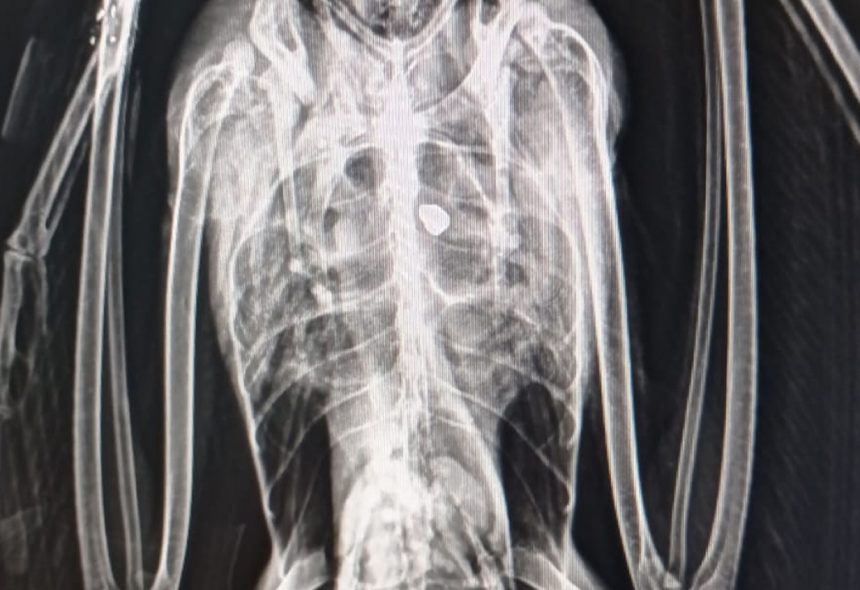

Para la identificación de amenazas antropogénicas para la conservación de las especies se están llevando a cabo inspecciones aleatorias en playas de Málaga en busca de cadáveres. Por otro lado, se ha solicitado la colaboración al organismo público de limpieza de playas para que reporte todos los orillamientos de aves que encuentren en las playas durante su limpieza.

El estudio de aves orilladas ha mostrado cambios en las causas de mortalidad, destacando el síndrome parético y residuos de pesca recreativa. También se han registrado episodios de inanición en álcidos tras tormentas atlánticas.